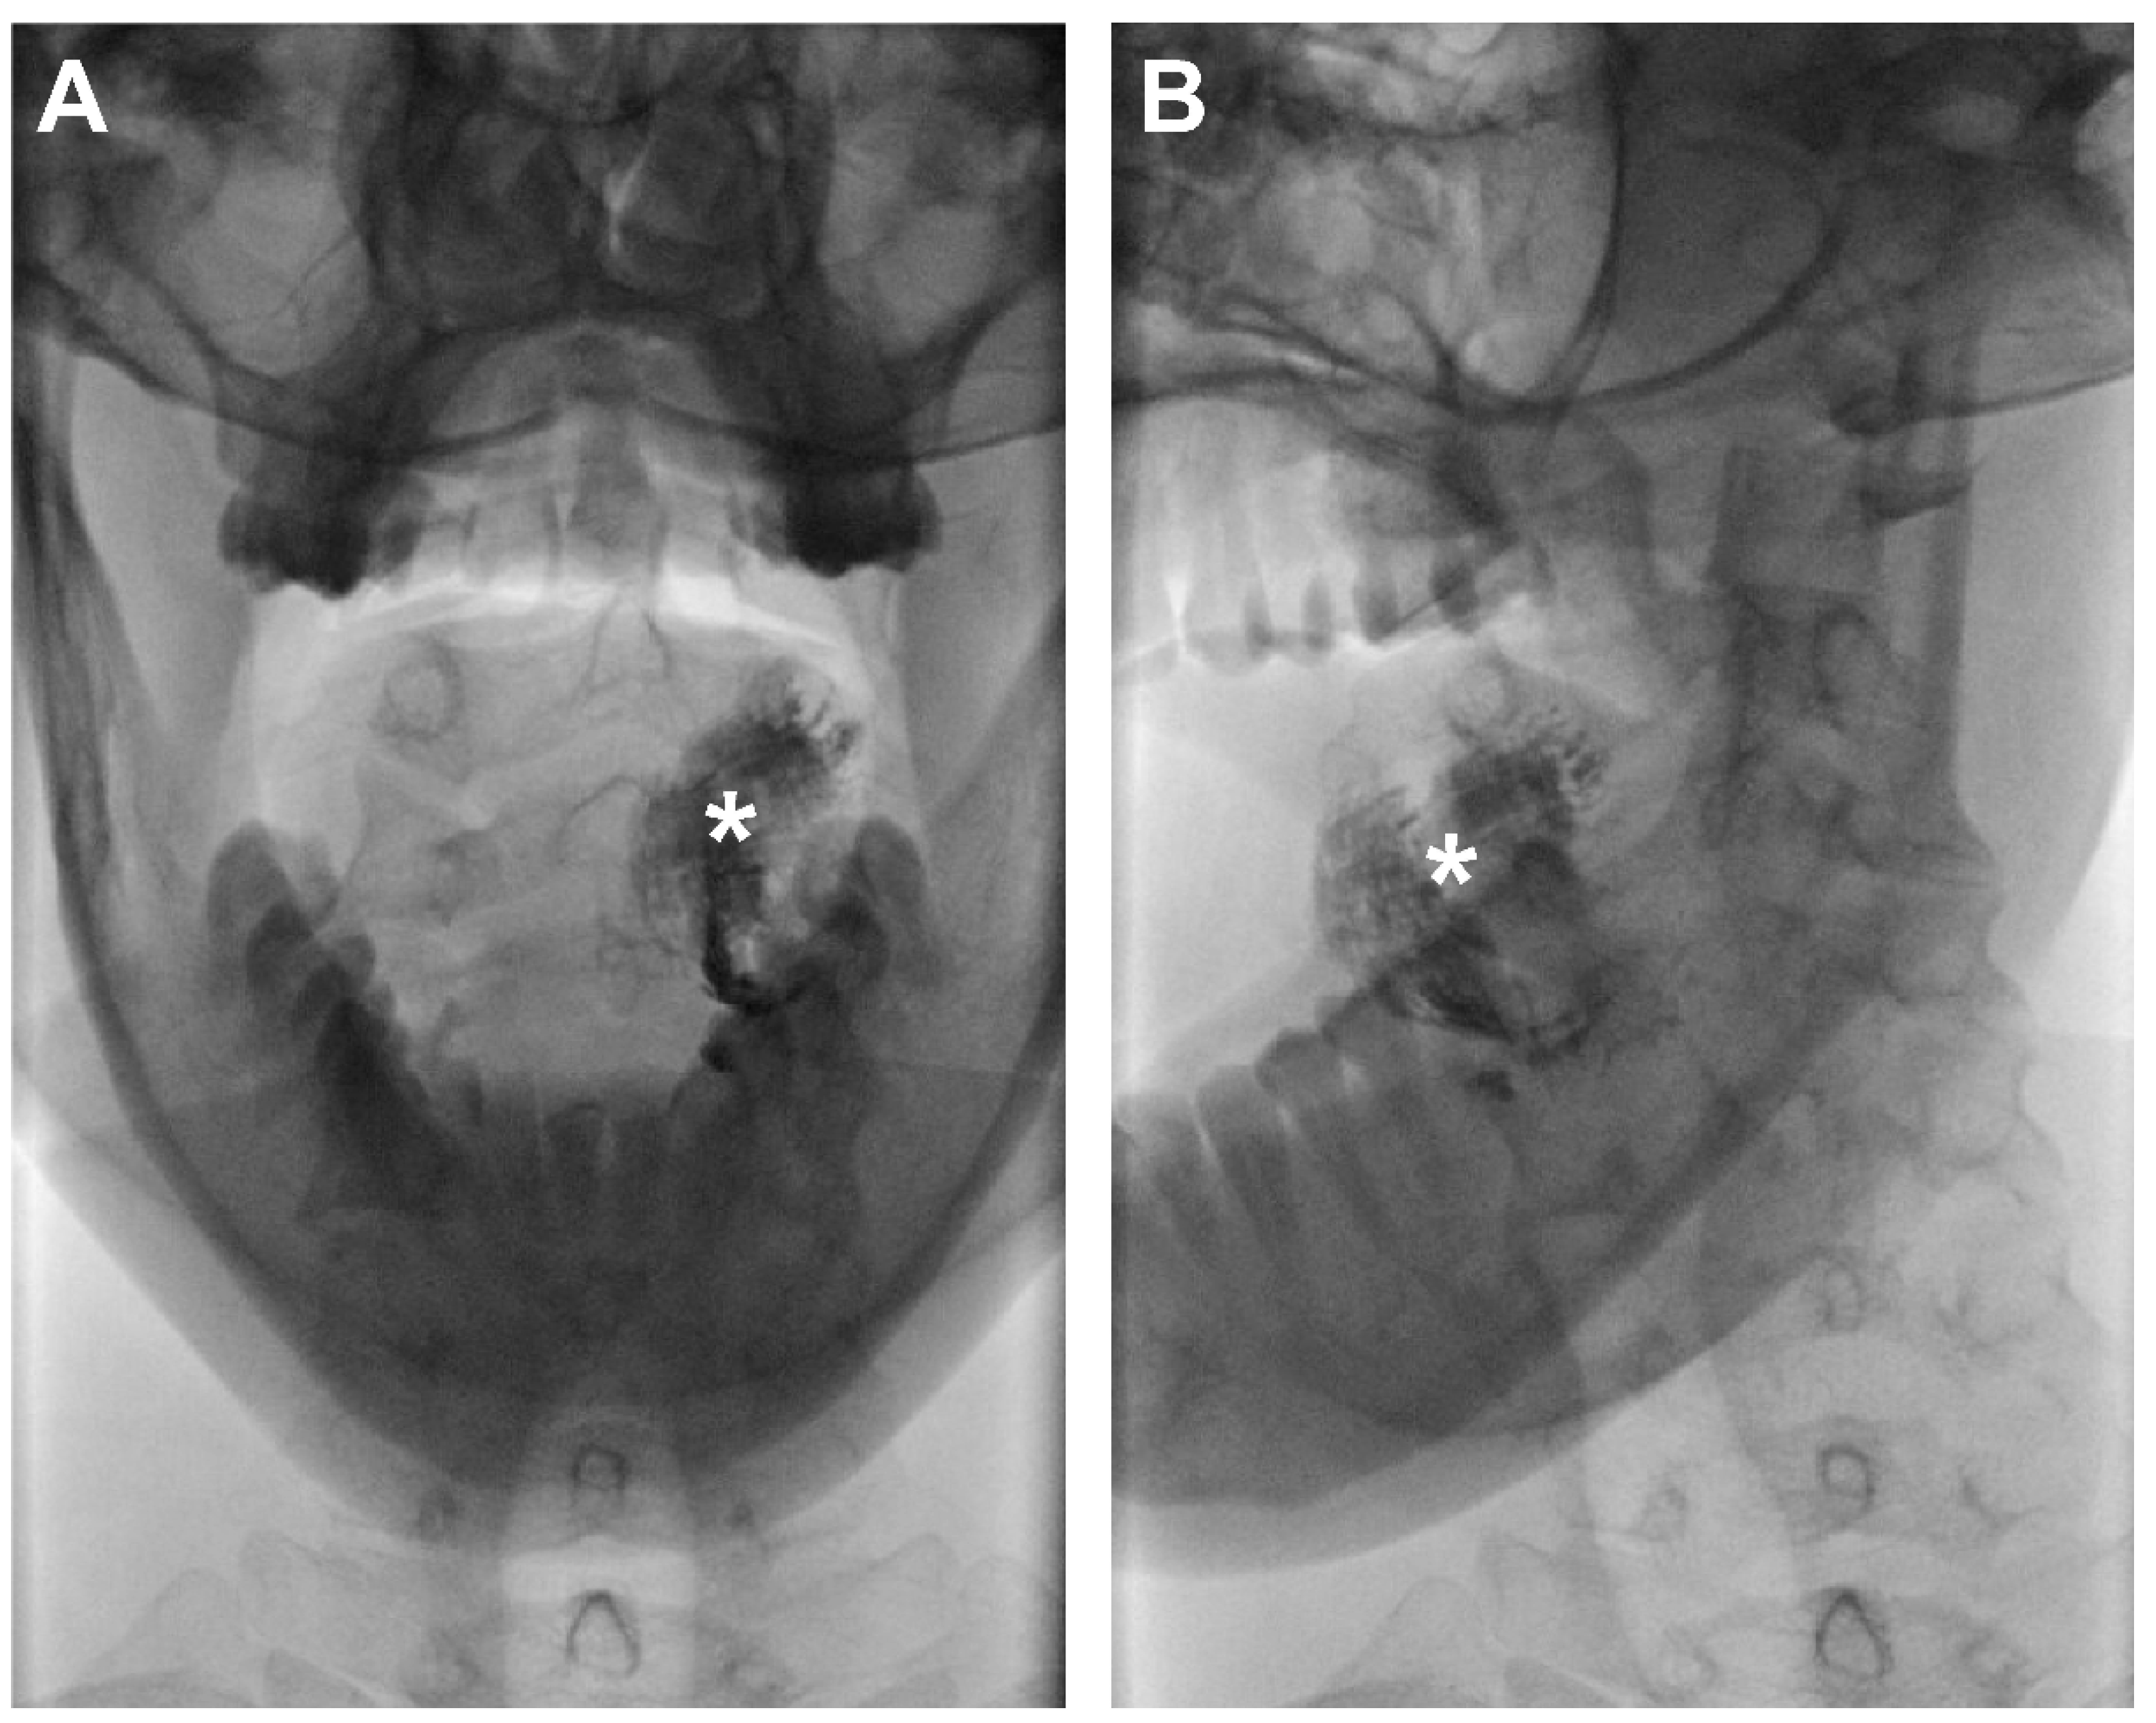

1. Introduction

2.2. Study Design

2.4. Scintigraphy and SPECT/CT